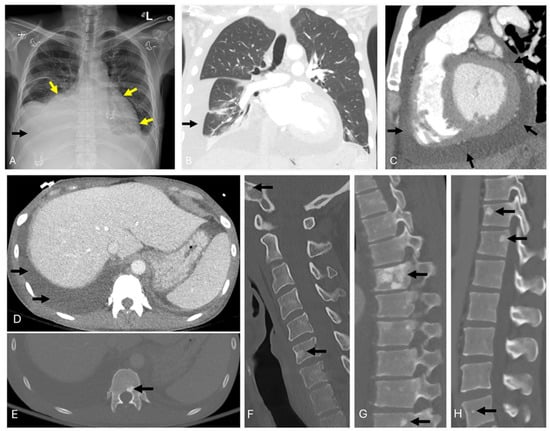

3.1. POEMS Syndrome